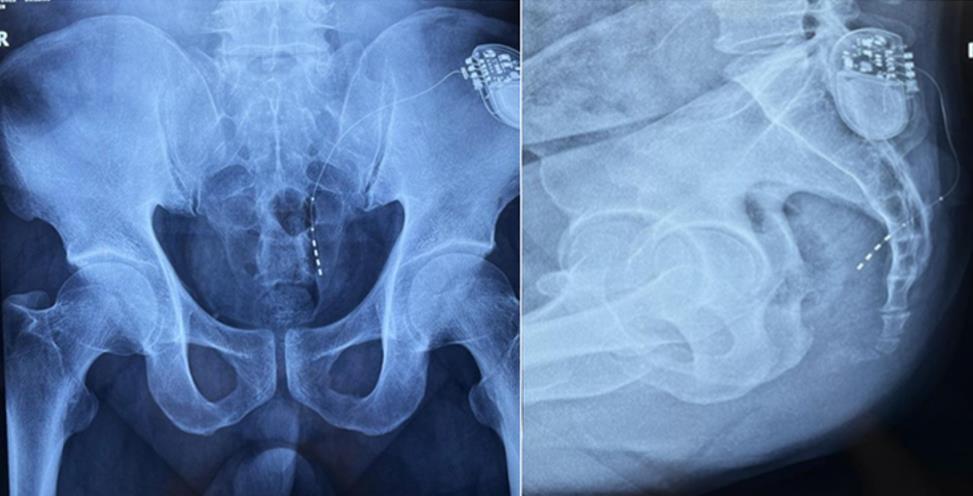

患者術(shù)前影像

該患者兩年前被診斷患有膀胱過度活動癥(OAB),出現(xiàn)嚴重尿頻、尿急、尿細線等癥狀,醫(yī)生為其做了骶神經(jīng)調(diào)控手術(shù)。近期,患者癥狀又開始加重,生活質(zhì)量受到影響,為減輕癥狀,改善生活,患者前往南醫(yī)大二附院就診。衛(wèi)中慶主任及其團隊在查看患者病情后,決定重新調(diào)整電極刺激位置,將刺激點由原左側(cè)骶4神經(jīng)孔改為骶3神經(jīng)孔,通過新的神經(jīng)調(diào)節(jié)順利地改善了癥狀。